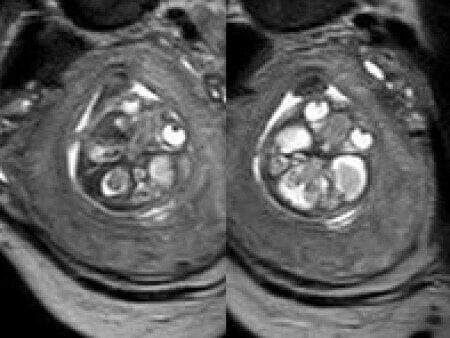

We present a case of agenesis of the cavum septum pellucidum (CSP).

At 20 weeks, detailed ultrasound under conditions of severe oligohydramnios demonstrated absence of the typical box-shaped anechoic structure of the cavum septum pellucidum (CSP). The frontal horns of the lateral ventricles appeared narrow and pointed, giving the characteristic “bull’s horns sign.” Multiplanar and 3D reconstructions confirmed the presence of the corpus callosum, while the CSP was absent. Other midline and posterior fossa structures appeared normal. The optic chiasm was partially visualized, although assessment was limited by technical conditions. Fetal magnetic resonance imaging (MRI) was subsequently performed and confirmed isolated agenesis of the CSP with preserved corpus callosum and posterior fossa structures. The optic chiasm and pituitary stalk are visible in the sellar region, but the pituitary gland itself is not clearly identified in the sella turcica as it is a very small structure. No additional central nervous system anomalies were detected.